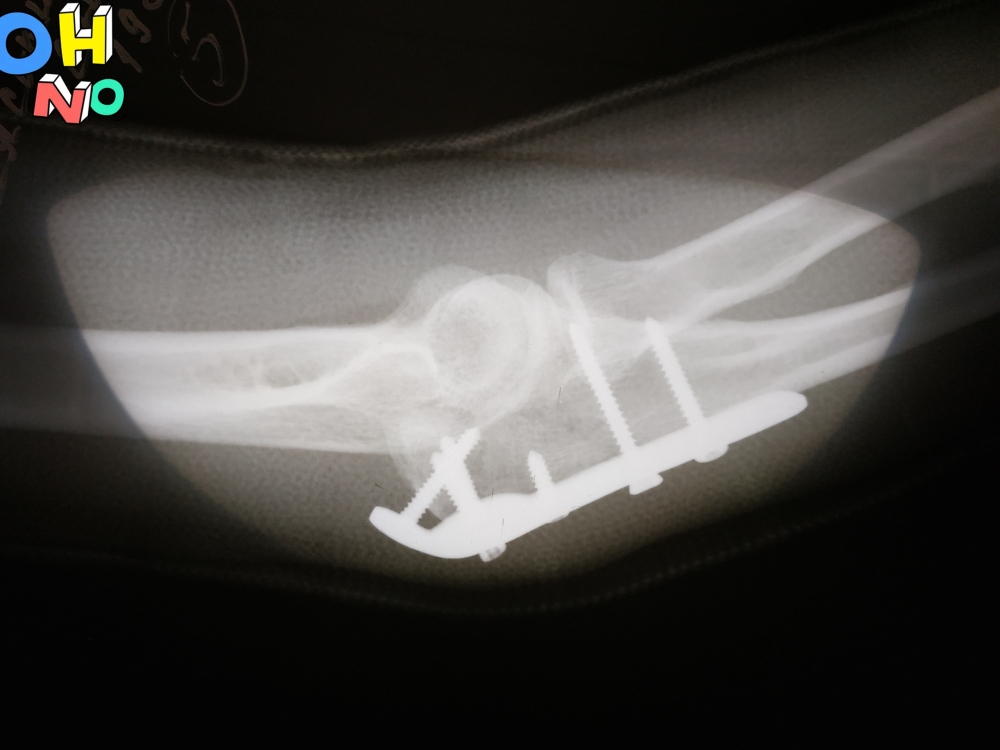

Перелом локтевого отростка, МОС 28.11.19. Снят гипс 27.12.19. Не разрабатывается рука. В чем причина, непонятно.

Угол сгибания локтя примерно 110-150 гр., с момента снятия гипса прогресса практически нет (ЛФК ежедневно,несколько раз в день). Встал вопрос, возможно, рука больше и не согнется пока пластина внутри? Или же, нужно просто больше времени?Буду очень благодарна за ответы

• Кликните для загрузки файла Снимок боковой1.jpg